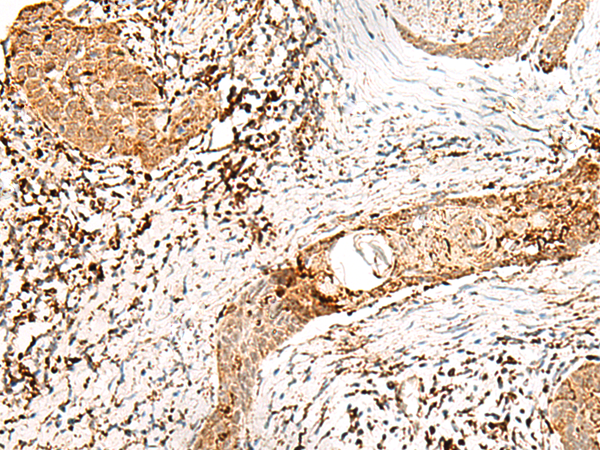

分类: 科研抗体货号: P00217别名: p94; CANP3; LGMD2; nCL-1; CANPL3; LGMD2A应用: IHC反应种属: Human, Mouse, Rat